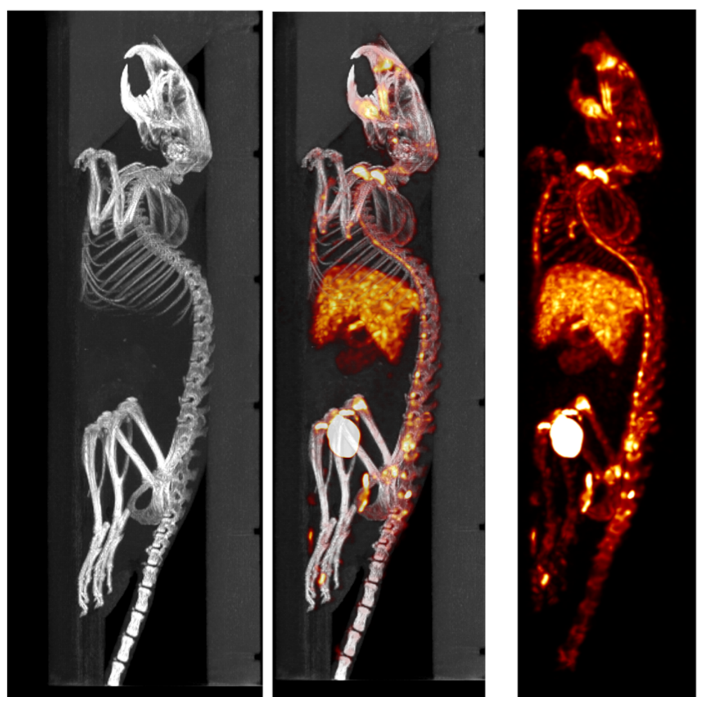

3、Bone SPECT imaging

SPECT/CT combination images, bone imaging of mice: 99mTc-HDP, 94.35MBq (2.55mCi) @start acquisition, acquisition time of 60min.

SPECT/CT combined imaging of bone in rats: 99mTc-HDP, 200MBq, acquisition time 45min.